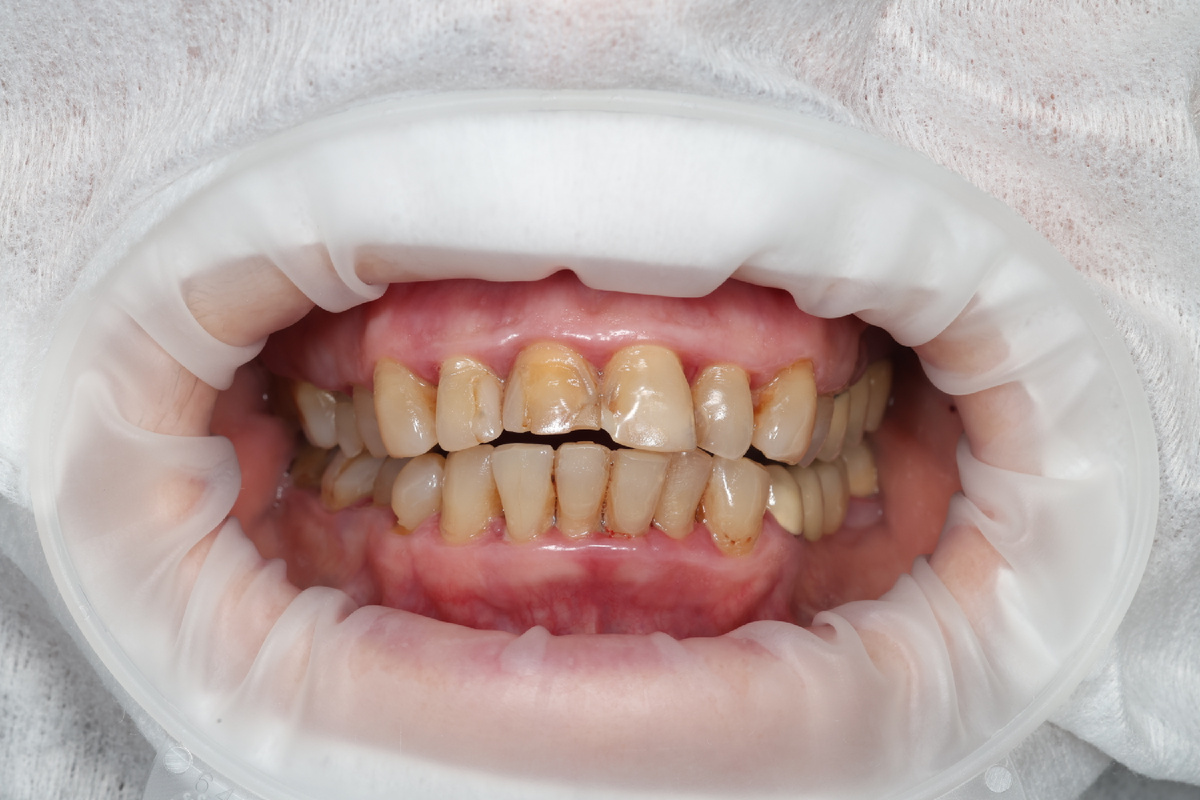

С коронками:

Тяжёлая степень тяжести К05.3

И вот вся проблема тех, чьи фото я показала выше - поддесневые зубные отложения. Именно они довели ткани пародонта до краха. Если не будут идеально очищены корни у пародонтологических пациентов, получим оголение корней, подвижность зубов и закончится это печально.

Тактика работы УЗ-скейлером при наличии коронок и виниров - не прикасаемся к реставрациям, трогаем ТОЛЬКО корни зубов. На корнях, напоминаю, реставраций нет (не должно быть).